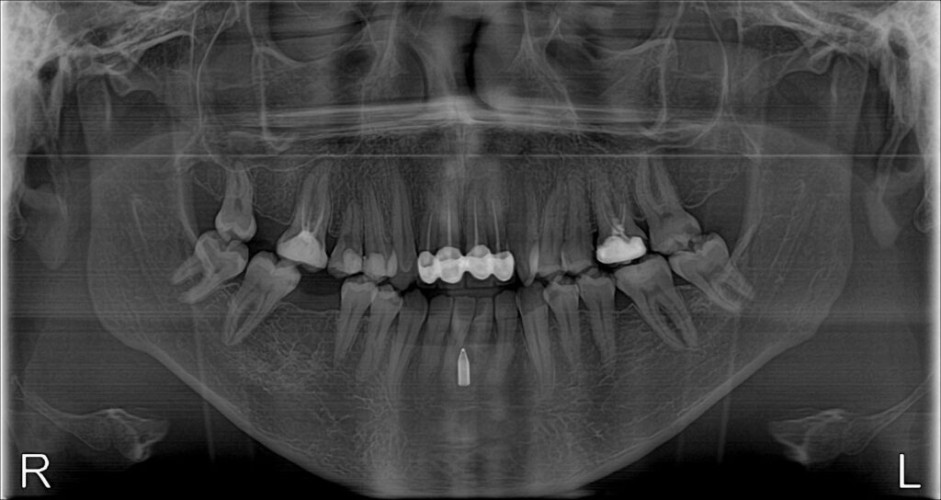

وذكر تجمع القصيم الصحي أن مريض ثلاثيني حضر عيادة الأسنان وهو يشكو من التهابات وآلام في ضرسه، مما استدعى عمل الفحوصات والاشعة اللازمة له والتي بينت وجود جسم غريب “رأس قلم” بين ثنايا اللثة في الفك السفلي، مما جعل الفريق المعالج يسارع لإجراء عملية جراحية لاستخراج الجسم الغريب استغرقت نصف ساعة تكللت بالنجاح ولله الحمد حيث تخلص فيها من الجسم الغريب والتهابات اللثة المزمن.